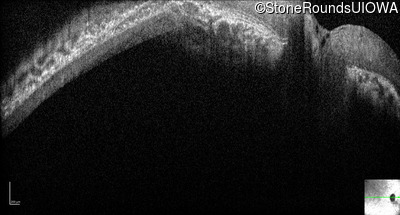

Age at visit: 18 years

This 18 year old woman was noted to have nystagmus shortly after birth. She has no recollection of any formed vision at any time in her life.

Diagnosis & molecular findings

Leber Congenital Amaurosis NMNAT1 Glu257Lys GAG>AAG Chr1:10034708-10042182del AR